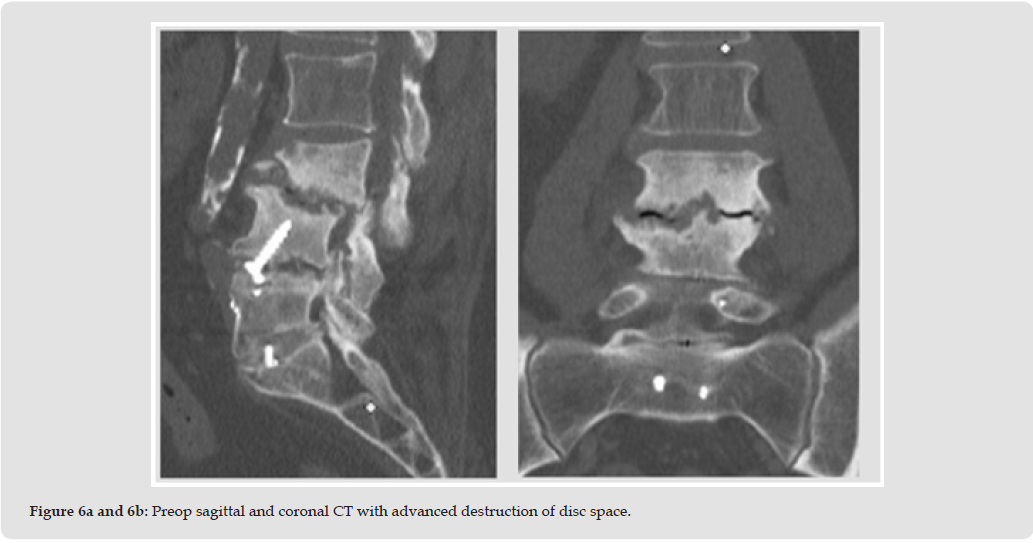

The patient is a 64-year-old male with a history of diabetes mellitus and previous L4-S1 spinal fusion surgery. He presents with intractable back with inability to stand and ambulate independently. The patient has severe bilateral anterior thigh pain and anterior leg pain radiating to the feet. He is ambulating with a kyphotic gait and exhibits weakness with quadriceps extension bilaterally measuring 4/5 on manual muscle testing. The L3-4 disc space degeneration was not seen on radiographs from 6 months prior (Figure 5). Preoperative CT (Figures 6a & 6b) immediately preceding surgery exhibits bony destruction at L3-4 with endplate irregularities and listhesis, which is a dramatic change compared to his radiographs. The patient was indicated for an L3 corpectomy with T10- pelvis fusion for decompression and stabilization. L3 corpectomy with long-segment fixation from T10–pelvis was performed and a titanium expandable cage at L3 was placed and was filled exclusively with (Osteoflo® Hydrofiber). Intraoperative cultures to rule out infection as a cause of his bony destruction were obtained. The intraoperative cultures eventually grew Pseudomonas aeruginosa. Postoperative x-rays (Figures 7a & 7b) showed appropriate spinal alignment and CT at 6 months after surgery had fusion through the corpectomy cage (Figures 8a & 8b).